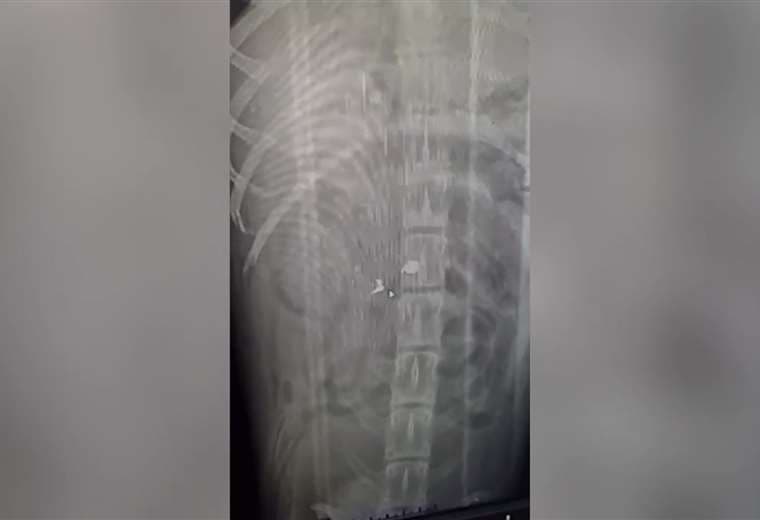

“Creí que tenía una fractura, pero al trasladarlo a la clínica veterinaria nos indicaron que no era fractura, sino una herida por proyectil. Ahora Canelo deberá someterse a una resonancia para determinar si el balín afectó la médula espinal.

"Si el proyectil le afectó la médula, solo hay dos cosas que podemos hacer: que una familia lo adopte para que lo cuide y le dé las mejores atenciones y, si no, hay que aplicarle la eutanasia, pero esperamos que haya buenas noticias mañana cuando nos den el resultado final de su estado de salud", agregó Villanueva.